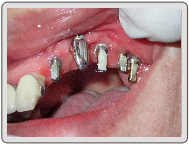

微創植牙-陳小姐

治療過程

置入植體